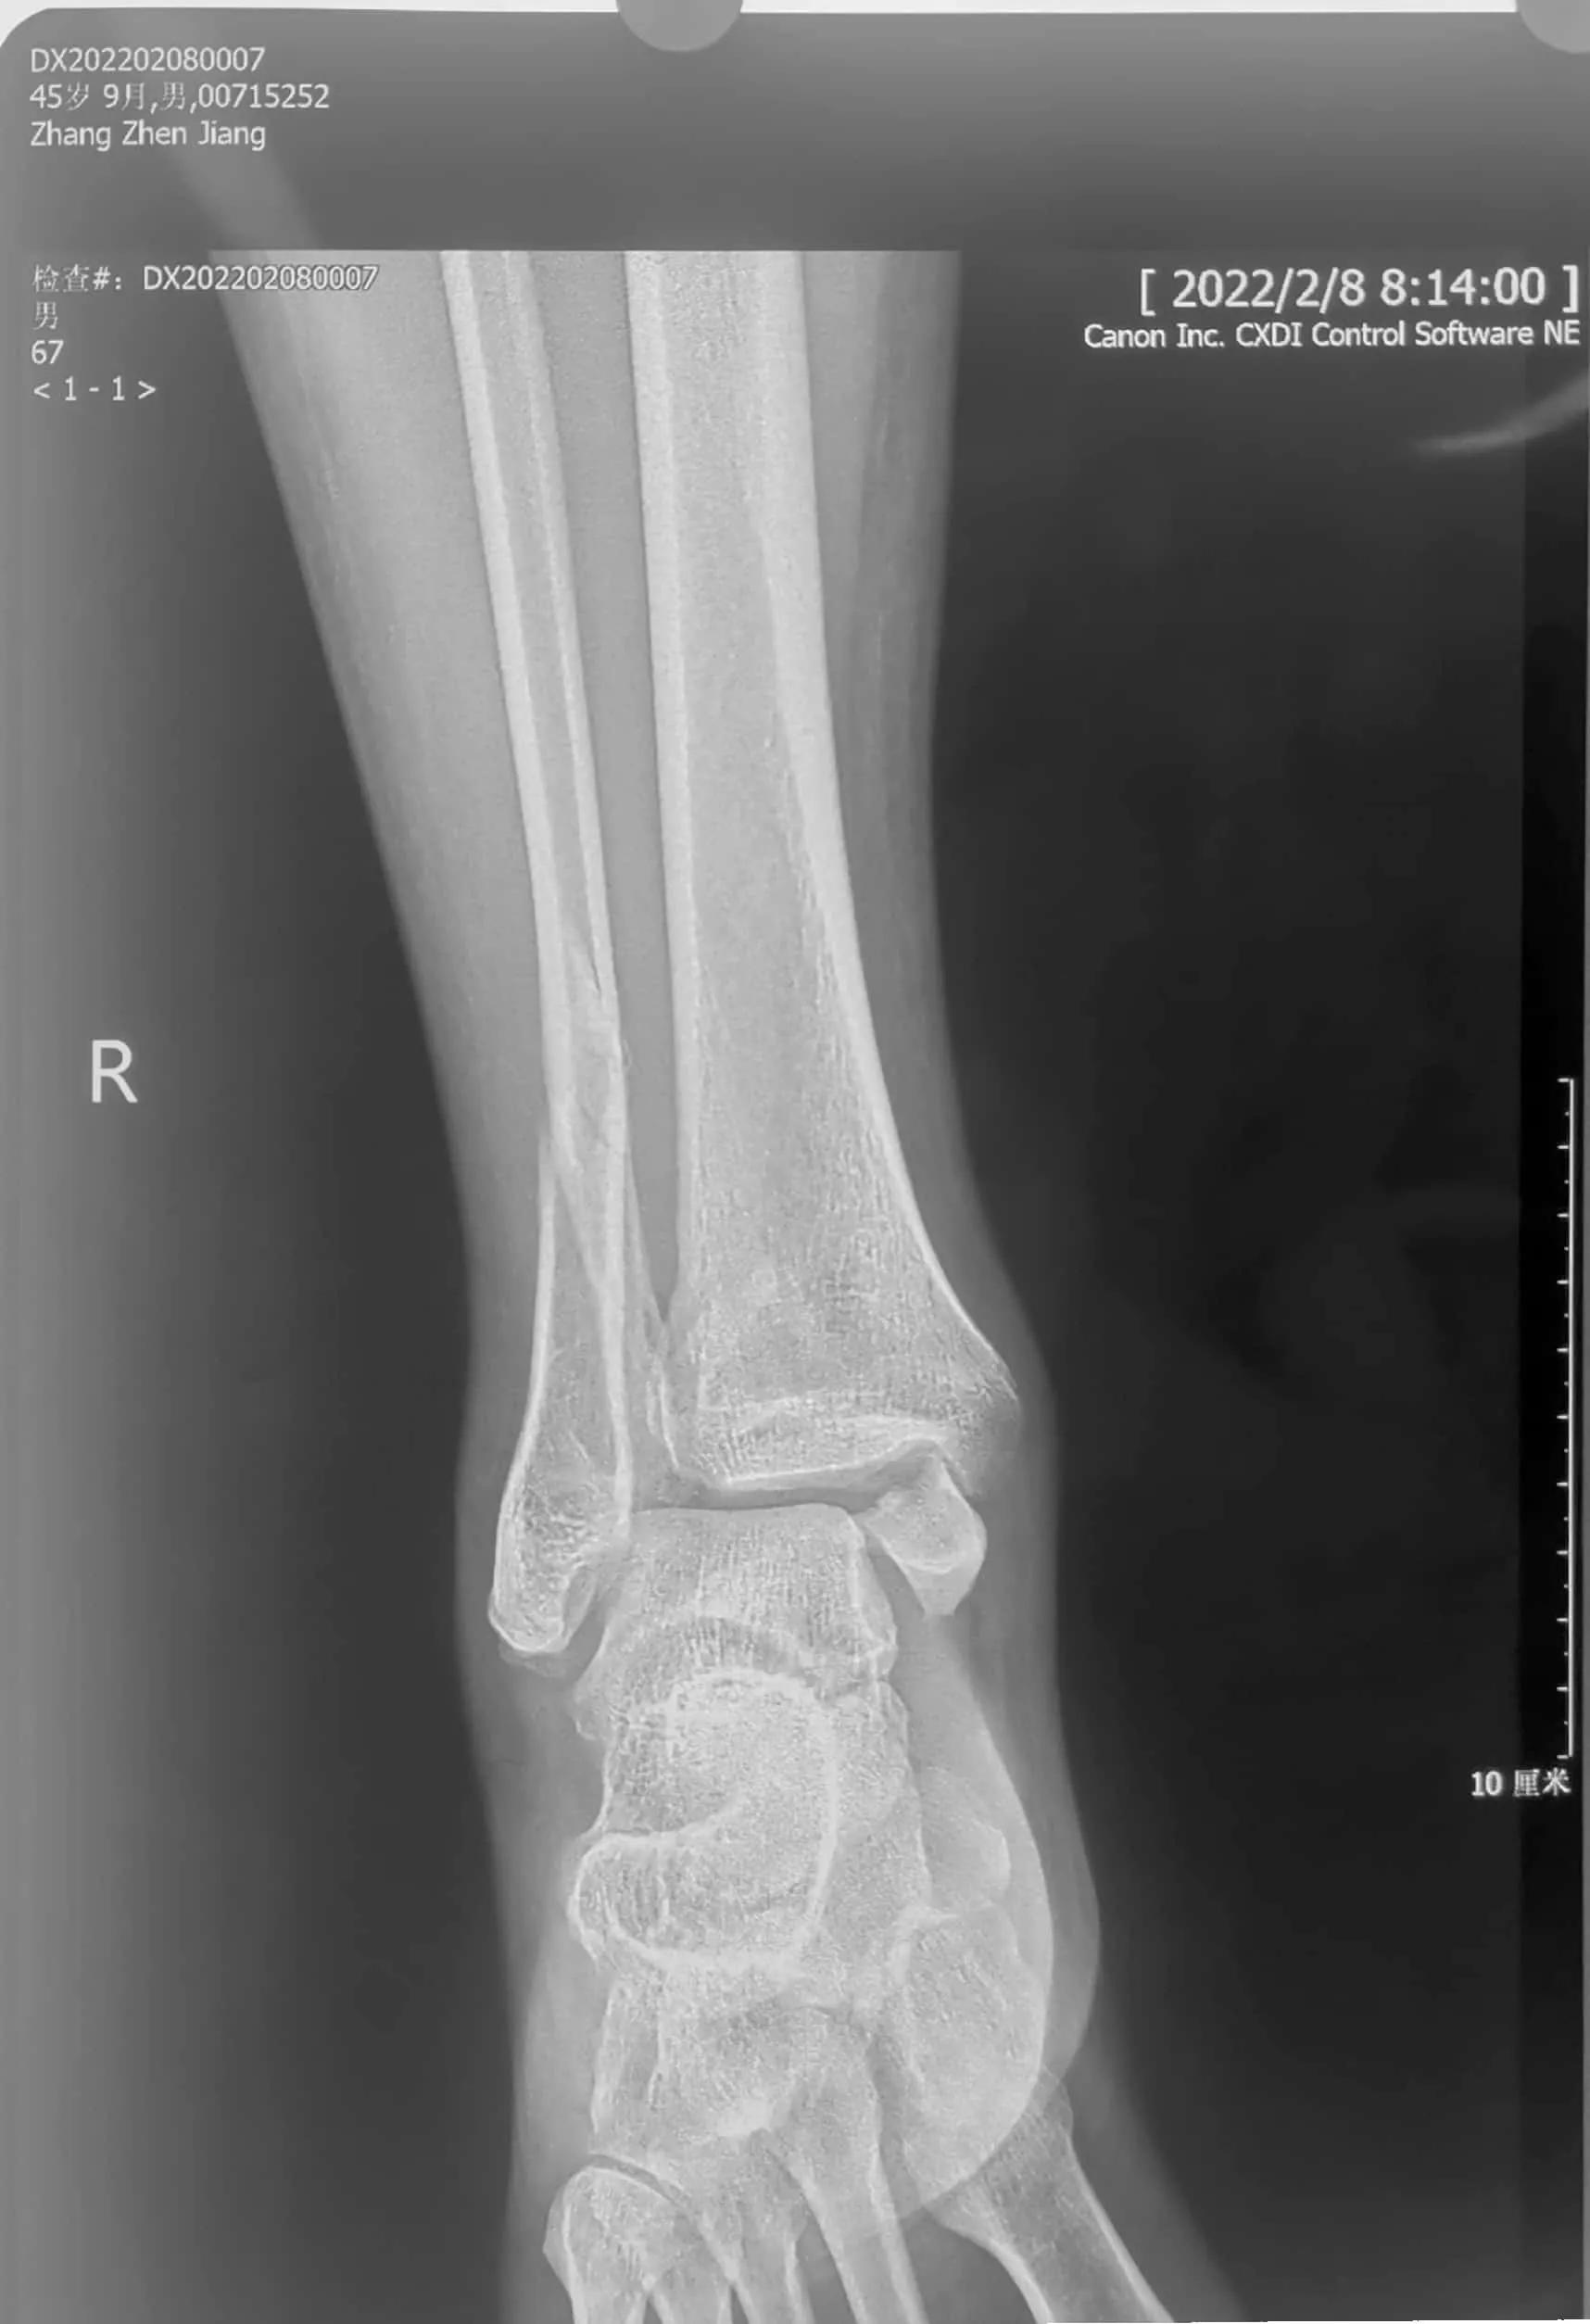

45岁,男性,2022年1月20日,也就是春节前10天不慎扭伤踝关节,过了两天到医院检查,诊断踝关节骨折。就近住院了,据说因为受伤太肿胀了,又临近春节,竟然让患者出院回家休养。17天了,患者仍疼痛难忍,踝关节肿胀。昨天来到我们医院,又拍了一次片子,竟然还和第一次检查时的片子一样,踝关节骨折脱位,内踝交锁!

这个踝关节骨折够严重的吧!